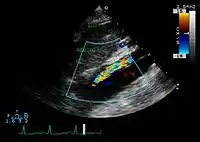

Ultrasound

The transesophageal echocardiogram (TEE) is a good test in the diagnosis of aortic dissection, with a sensitivity up to 98% and a specificity up to 97%. It has become the preferred imaging modality for suspected aortic dissection. It is a relatively noninvasive test, requiring the individual to swallow the echocardiography probe. It is especially good in the evaluation of AI in the setting of ascending aortic dissection and to determine whether the ostia (origins) of the coronary arteries are involved. While many institutions give sedation during transesophageal echocardiography for added patient comfort, it can be performed in cooperative individuals without the use of sedation. Disadvantages of TEE include the inability to visualize the distal ascending aorta (the beginning of the aortic arch), and the descending abdominal aorta that lies below the stomach. A TEE may be technically difficult to perform in individuals with esophageal strictures or varices.